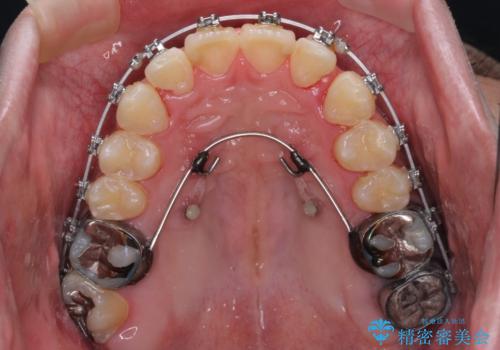

- 矯正装置

- メタルブラケット

下顎に対して上顎歯列が全体的に前方に位置しており、特に右側の奥歯の咬み合わせの前後のズレが大きいため、補助装置を用いて咬み合わせを改善することとしました。